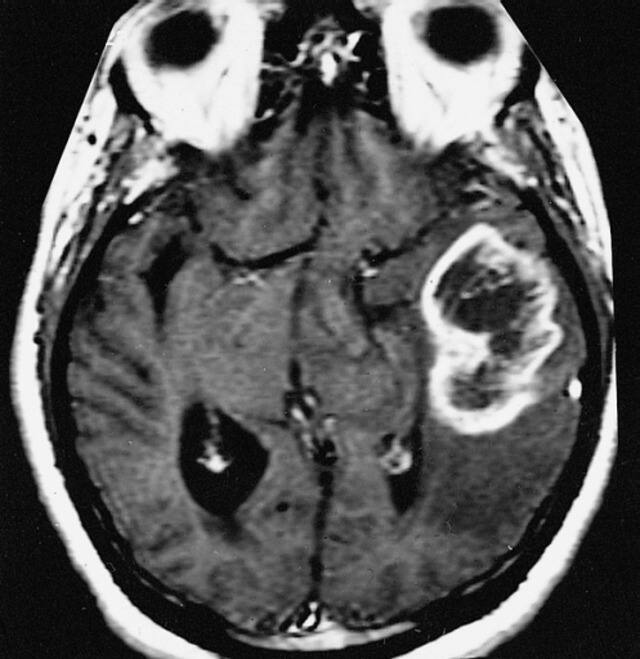

Glioblastoma is the most common malignant brain tumor manifesting with a highly aggressive clinical course which is invariably lethal. The incidence varies from 3.19 to 4.17 per 100,000 population as per various studies, affecting adults more than the paediatric population. Though reported across different age groups, international studies have proposed a median age of 64 years. The disease peaks almost a decade earlier in the Indian population which is likely to be due to a larger proportion of younger people in India and a lower overall life expectancy. Men are more commonly affected than women and show a rapidly worsening clinical course. This is linked to testosterone which aids in tumor progression while estrogen in women plays a protective role. Survival is extremely dismal with most patients succumbing to the illness in one-two years interval despite multimodality treatment. [caption id=“attachment_10934161” align=“alignnone” width=“640”]  Glioblastoma Multiforme as seen here by magnetic resonance imaging, the glioblastoma multiforme usually exhibits a “ring” or “ring-like” zone of contrast enhancement around a dark central area of necrosis. Wikimedia Commons[/caption] Glioblastomas can arise de novo as primary malignant tumors or present as secondary progression in a previously low-grade malignant glioma. These most commonly involve the frontal and temporal lobes with increased incidence seen in patients previously exposed to radiation or having impaired immune response. Hereditary cancer syndromes like Li-Fraumeni and Lynch syndrome are also associated with exponentially increased susceptibility. Clinical presentation varies depending on the area of brain involved but the most common symptoms include persistent headaches, vomiting, visual disturbances like double vision and blurring, speech difficulties, changes in mood and behaviour and an overall deterioration in cognitive and memory functions. Seeking medical attention early is imperative, since the tumor is highly expeditious in its ability to infiltrate the surrounding normal brain tissue causing rapid deterioration. Initial diagnosis is not a challenge in most cases with pathognomic findings on radiology and histopathology. Further molecular tests for confirming histopathological diagnosis, prognostication of tumor and identifying treatment targets are mandatory with the most commonly implicated alterations being mutations/variations involving genes like IDH, MGMT, EGFR, PTEN, TERT, TP53, WT1, 7p (gain) and 10q (loss), H3F3A, ATRX, GATA4 and fusions involving FGFR and NTRK. The treatment revolves around maximal safe resection of the tumor practicing caution to preserve as much normal surrounding brain tissue as possible, for proper neurological functions. Since the cancer margins are cuffed by migrating cells which infiltrate the normal surrounding brain, it is impossible to completely excise the mass. This is thus, followed by adjuvant radiotherapy, and concurrent chemotherapy with a drug called Temozolomide, both of which aim to kill the remaining cancer cells and prevent recurrence. Treatment of Glioblastomas is extremely challenging due to localisation of the tumor and hindrance to drug delivery caused by blood-brain barrier and disruption of blood supply along with peritumoral edema. Also the tumor itself is made of heterogenous molecular signatures, further contributing to its complexity and resistance to standard therapy. One glance at this journey of patients and caregivers is enough to give you an insight into the Herculean courage and resilience that both show against a fate where the odds are not in favour. The treatment is extremely taxing, met with numerous debilitating side effects and insufficient at this juncture to provide a cure. The aim still is to prolong productive life by as much time as possible. Given the low incidence, short survival, cognitive debilitation of patients and the overall turmoil to the family, collection of data for a prospective study is extremely difficult. This has resulted in relatively lesser research and industry interest when compared to other more prevalent cancers. But last few years have seen a change in this scenario due to the rising incidence and insightful recognition of the need to support the battle against this lethal enemy. The complex and baleful clinical course demands an urgent collective focus on research for newer, more efficacious targets and a cure, if possible. In US, a bipartisan group of senators came together in 2019 to commemorate the courage of those who lost the battle against this menace. The proposition was all the more personal especially after losing senators like John McCain, Ted Kennedy and Beau Biden, all of who succumbed to Glioblastoma. The cause was supported by the National Brain Tumor Society, which spearheaded the inaugural event on 17 July, 2019 to support the survivors and their loved ones, to remember those who lost their lives, and to honour those who are working tirelessly to find an effective cure for this devastating illness. Thus was born, the Glioblastoma Awareness Day which is celebrated on the third Wednesday of July. Primarily a cause which originated in US, it resonates the exigency of finding a potent and viable treatment for this lethal disease. This year, the Glioblastoma Awareness Day will shine light on all these aspects on 20 July, 2022. The need to support the ones afflicted, to remember the ones who fought valiantly but are no longer with us, to create awareness about Glioblastoma at large and for diligent and detailed research aimed at finding a cure stays pivotal and necessitates a more global involvement in our endeavour to triumph against this notorious, life threatening illness. Dr Kunal Sharma is Associate Director & Head- COE and Histopathology, SRL Diagnostics Read all the Latest News , Trending News , Cricket News , Bollywood News , India News and Entertainment News here. Follow us on Facebook, Twitter and Instagram.